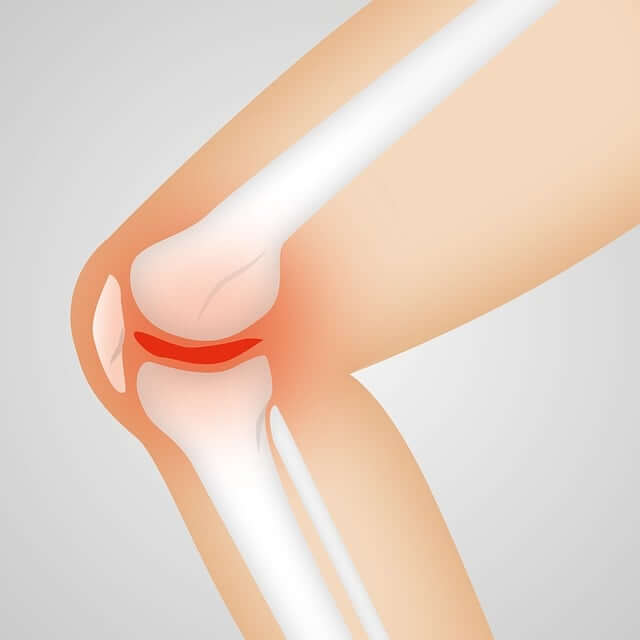

골괴사는 뼈로 가는 혈류가 차단되어 뼈 조직이 괴사하는 질환으로, 주로 대퇴골두(허벅지 뼈 머리 부위)에 발생합니다. 무릎, 어깨, 발목에도 드물게 발생할 수 있으며, 빠른 진단과 초기 치료가 예후에 큰 영향을 미칩니다.

관절염은 염증성 질환이고, 골괴사는 혈류 차단으로 뼈가 괴사하는 질병입니다. 증상은 비슷하지만 원인과 치료 방식이 다르기 때문에 정확한 진단이 필수입니다.

골괴사는 뼈로 가는 혈류가 차단되어 뼈 조직이 괴사하는 무서운 질환으로, 대퇴골두에 자주 발생합니다.